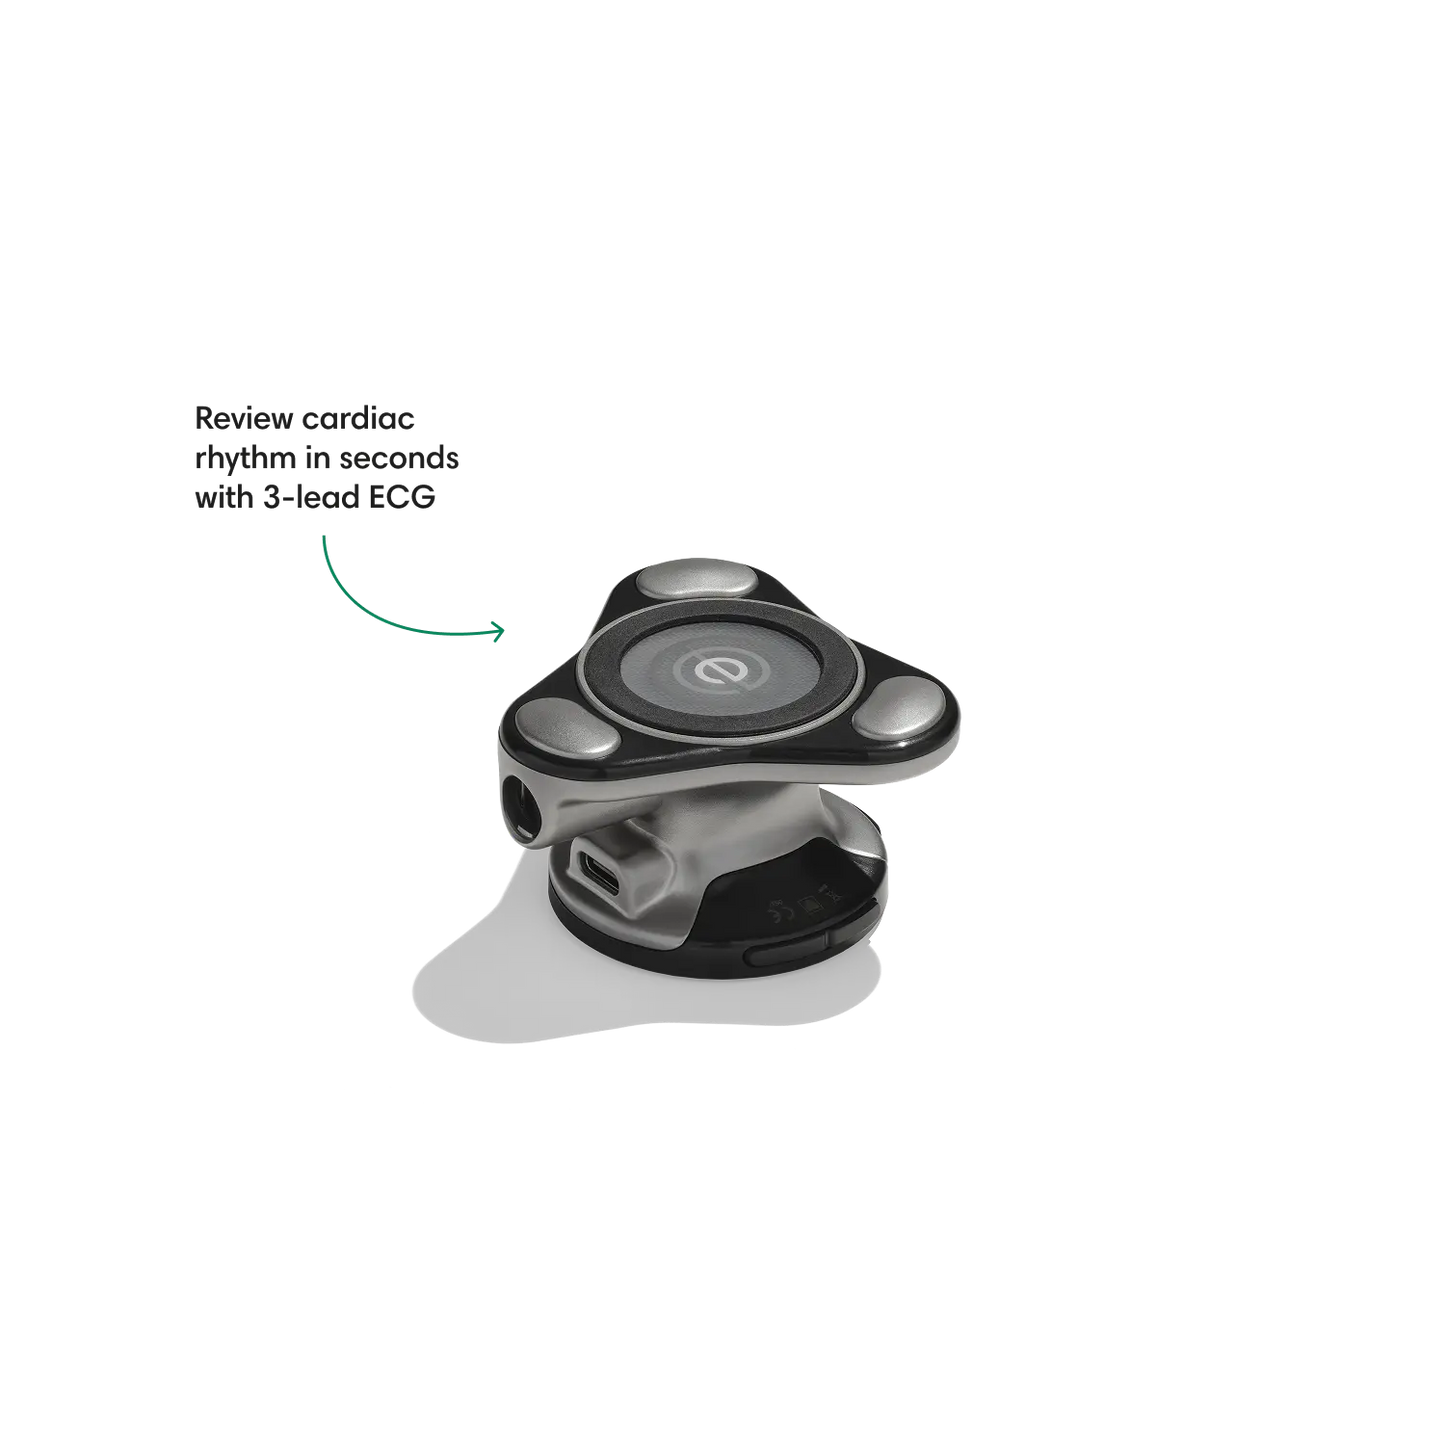

Go beyond sound alone.

For the first time ever, measure heart rate, visualize 3-lead ECG, and see detection results — right on a built-in, full-color display.